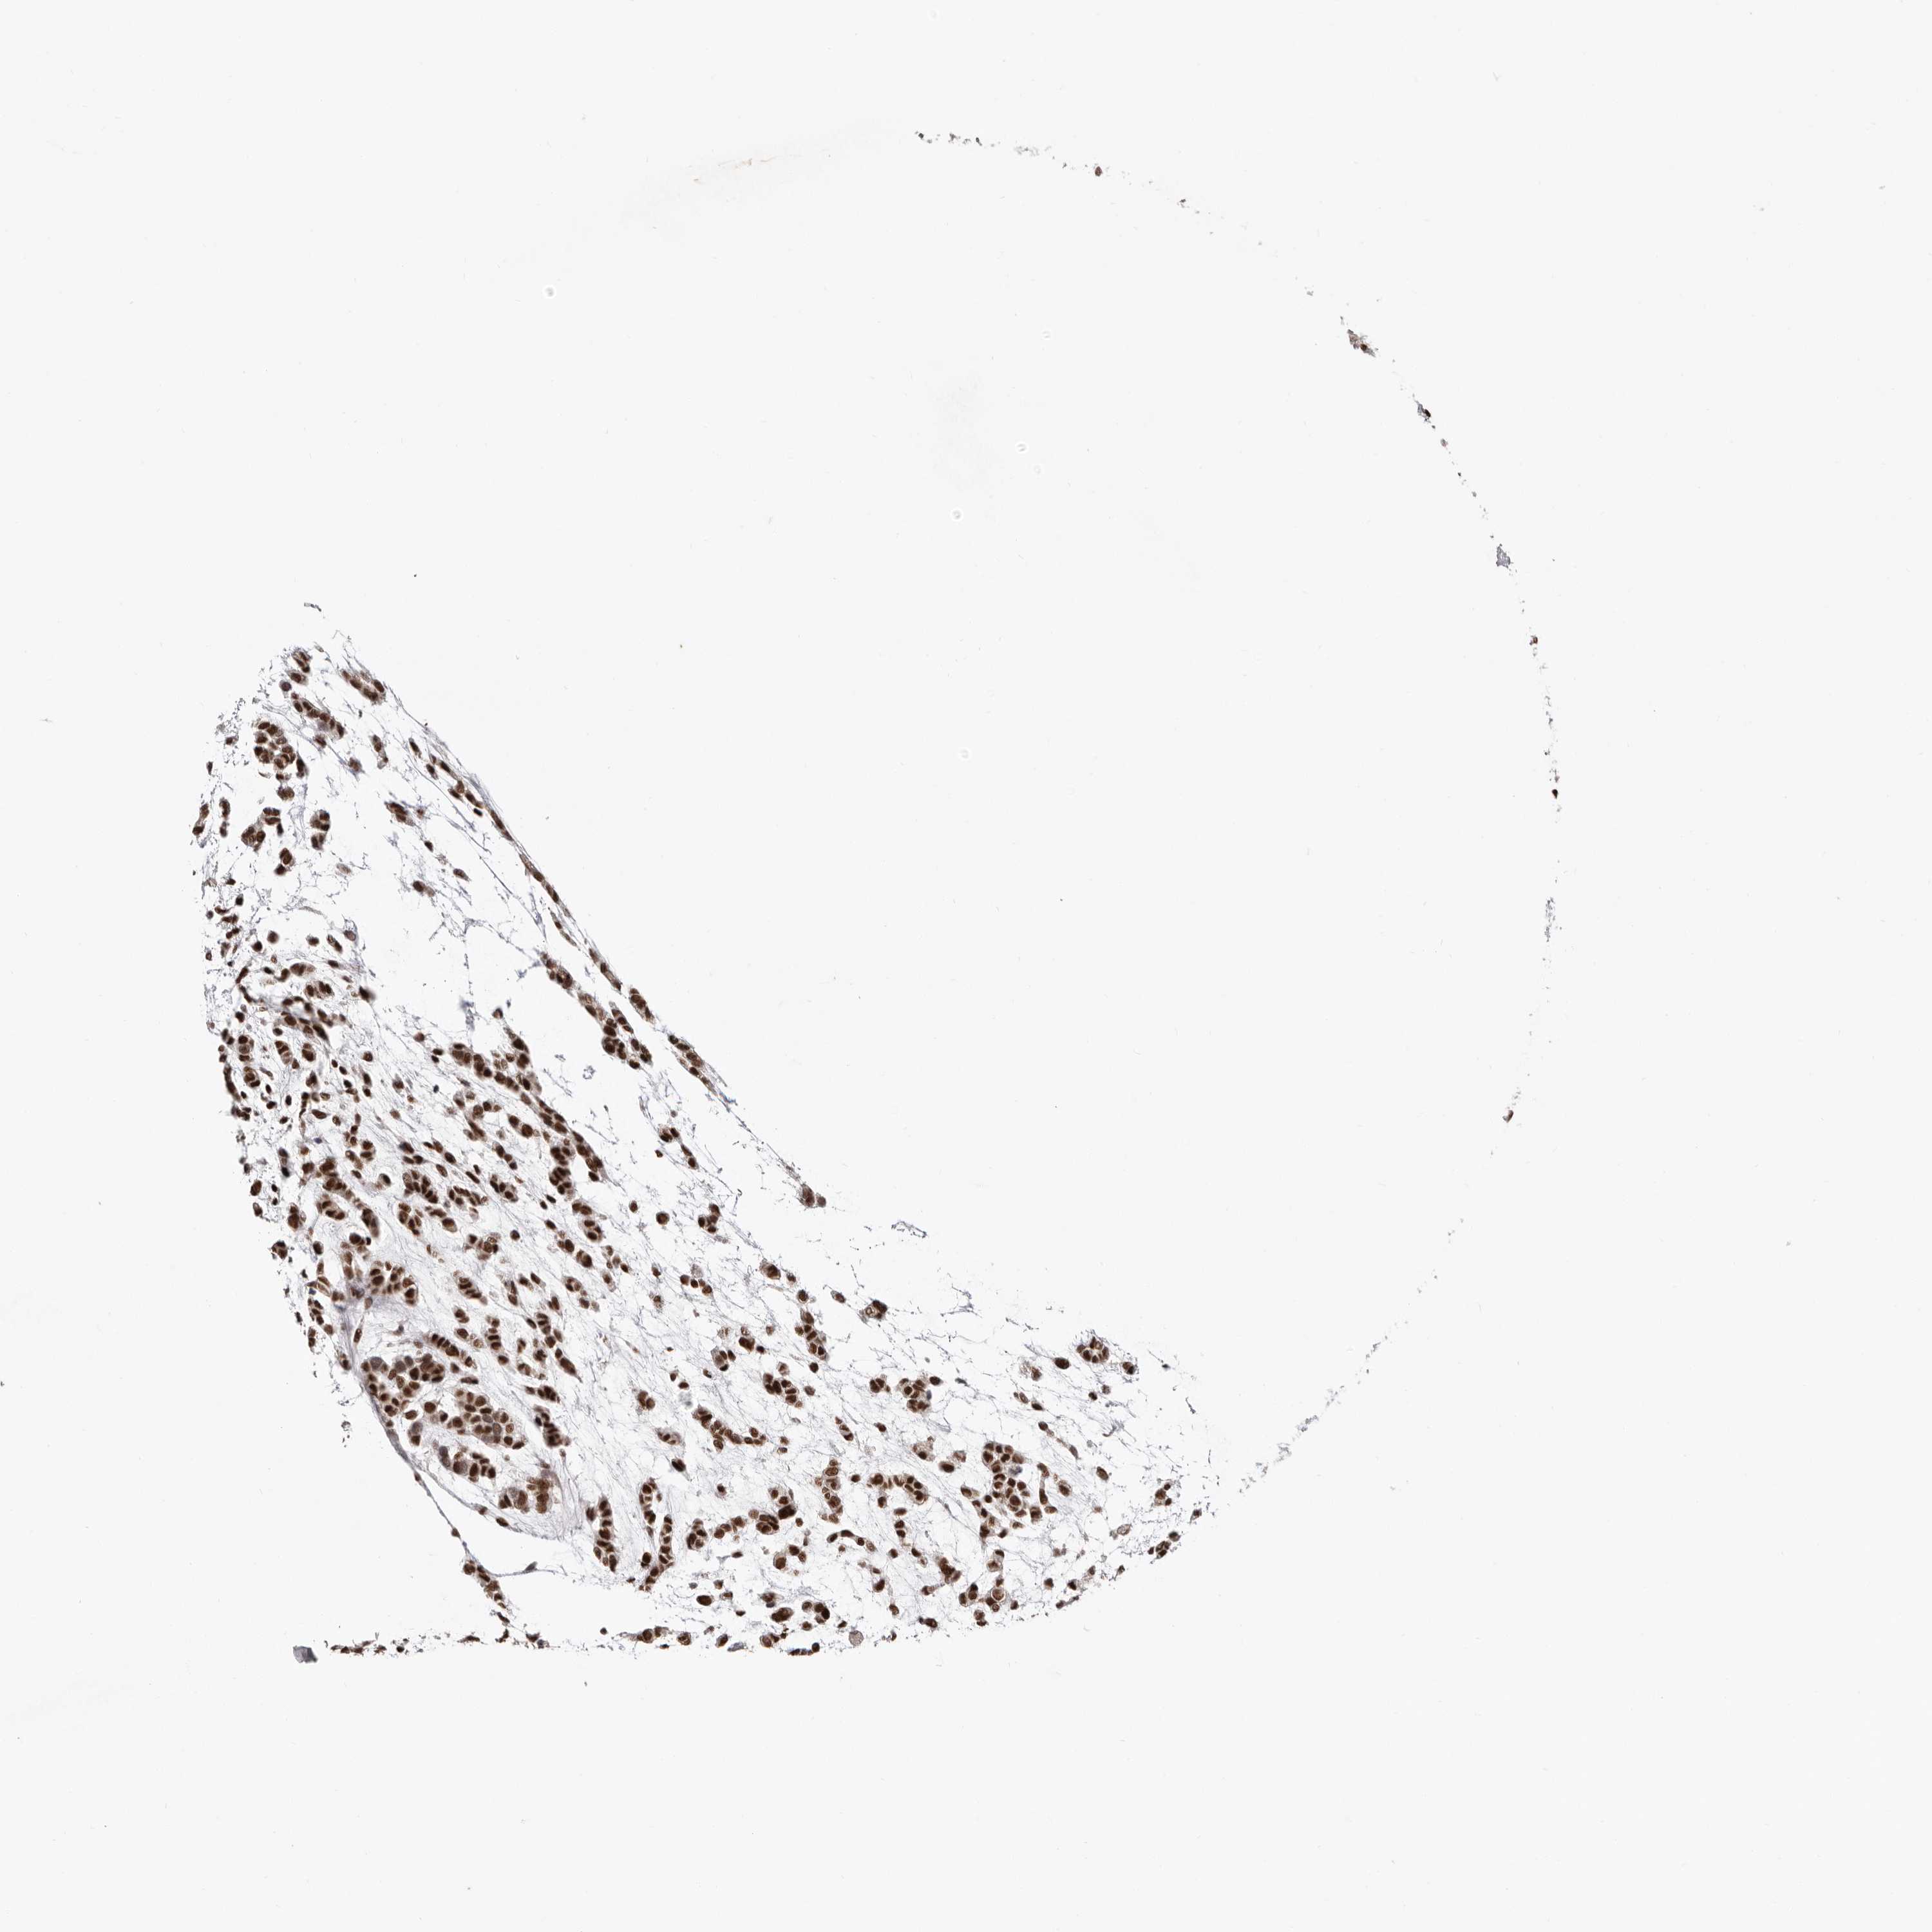

HEAD AND NECK CANCER - Protein expressioni

A mouse-over function shows sample information and annotation data. Click on an image to view it in a full screen mode. Samples can be filtered based on level of antibody staining by selecting one or several of the following categories: high, medium, low and not detected. The assay and annotation is described here.

Antibody stainingi

Antibody staining in the annotated cell types in the current human tissue is reported as not detected, low, medium, or high, based on conventional immunohistochemistry profiling in selected tissues. This score is based on the combination of the staining intensity and fraction of stained cells.

Each image is clickable and will lead to virtual microscopy that enables deeper exploration of all samples and also displays staining intensity scores, fraction scores and subcellular localization as well as patient and tissue information for each sample.

Antibody HPA028897

Staining

High

Medium

Low

Not detected

Intensity

Strong

Moderate

Weak

Negative

Quantity

>75%

75%-25%

<25%

None

Location

Nuclear

Cytoplasmic/membranous

Cytoplasmic/membranous,nuclear

Squamous cell carcinoma, NOS